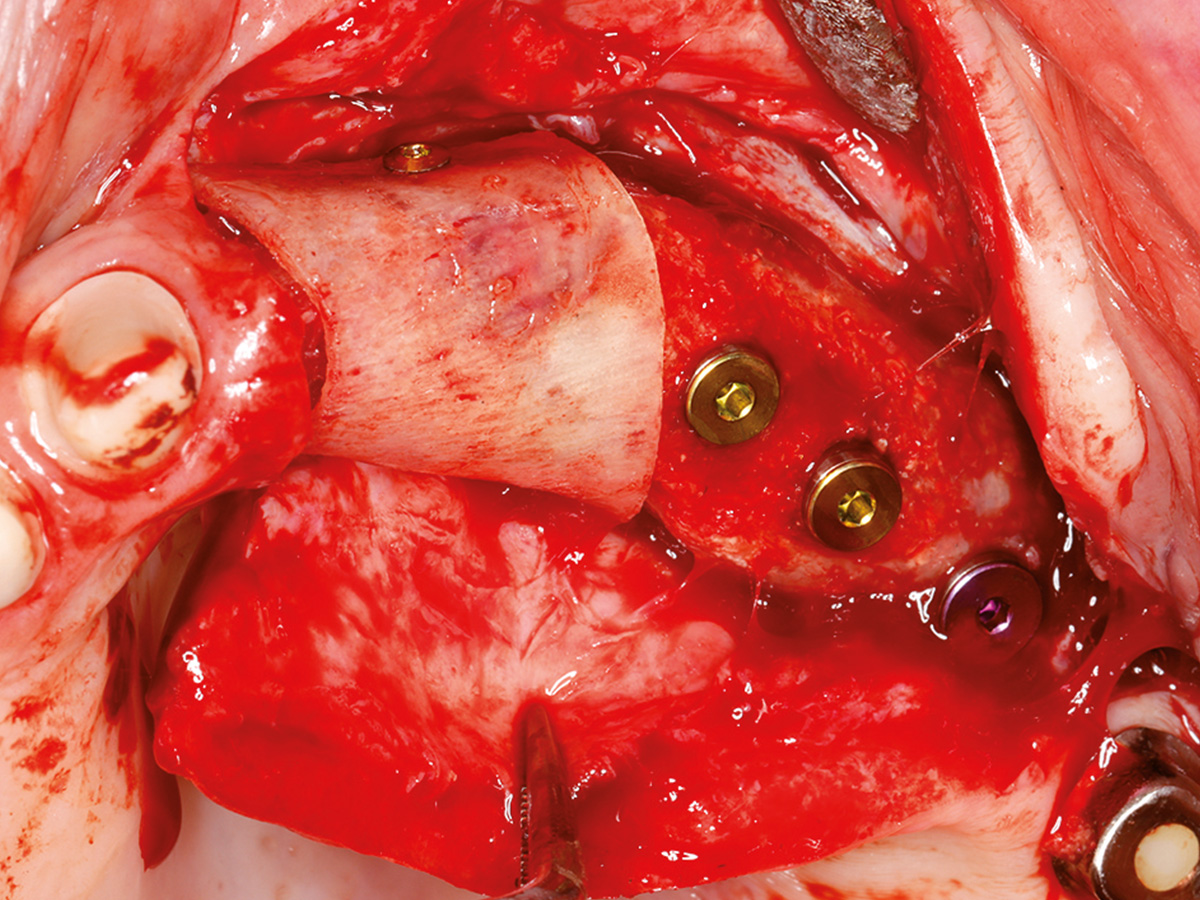

Osseodensifikation ist eine einfach zu erlernende Technik, die hilft, das Implantatlager zu verbessern. Besonders imOberkiefer, wo weicher Knochen häufig keine ausreichende Primärstabilität bietet, können mithilfe der Densah-Bohrer Verbesserungen erzielt werden, um eine reizfreie Einheilung derImplantate zu gewährleisten. Die aber wohl bemerkenswerteste Eigenschaft der Spezialbohrer ist, dass sich damit absolutminimalinvasive geschlossene Sinusaugmentationen durchführen lassen, was für Patienten sehr angenehm ist. Trotz technischer Innovationen muss in vielen Fällen zusätzlich augmentiert werden. Auch hier kommt den Materialien eine ganz besondere Bedeutung zu. Wird partikulär mit Knochenersatzmaterial augmentiert, müssen Membranen verwendet werden. Unzählige aufdem Markt befindliche Produkte haben sehr unterschiedliche Indikationsbereiche und variieren stark in Ergebnis und Handling.

In diesem Kurs wird das Handling mit der Bone Lamina samt Augmentation geübt. Danach sollte jeder Teilnehmer inder Lage sein, im Praxisalltag Knochen aufzubauen. Dazu isteine korrekte Schnittführung notwendig, die ebenfalls thematisiert wird. Damit ein Knochenaufbau erfolgreich einheilt, ist der spannungsfreie Wundverschluss zwingend erforderlich.Deshalb wird im Kurs auch besonderes Augenmerk auf spezielle Nahttechniken gelegt, die am Modell und am Schweinekiefer geübt werden.